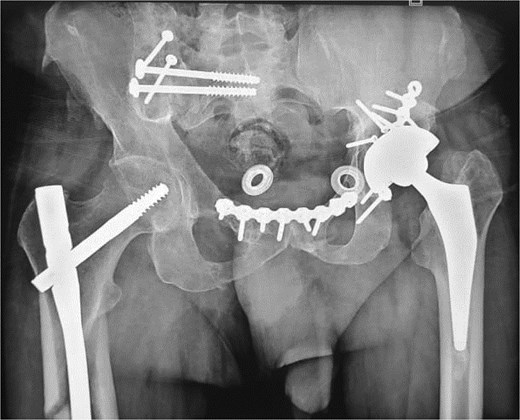

This was a 42-year-old male patient with no previous medical history who was admitted to the intensive care unit for treatment of polytrauma: severe chest trauma and pelvic trauma. During his stay in intensive care, the patient developed a pulmonary infection complicated by septicemia, requiring prolonged antibiotic therapy and thereby contraindicating any internal surgical fixation. After hemodynamic and respiratory stabilization, he was transferred to our department 40 days after the trauma with the following injuries: an unstable pelvic ring fracture classified as Tile-AO B1-2 [4]: disjunction of the pubic symphysis, disjunction of the right sacroiliac joint, and an ipsilateral crescent fracture classified as Kumar-Day 2 [5], along with a transverse–posterior wall fracture of the left acetabulum associated with a posterior dislocation of the hip, which was initially reduced but remained unstable. Fixation was performed using a Hoffmann II external fixator applied to the iliac crests with poor reduction (Fig. 1). He presented with complete weakness of the left foot dorsiflexors, with preserved sensation and no urogenital or abdominal complications. ORIF was performed in two stages, 5 days apart. The first stage consisted of performing the first two windows of the ilioinguinal approach: the lateral window to access the sacroiliac joint and the middle window to access the lower part of the sacroiliac joint and remove the osteofibrous callus. A Pfannenstiel approach was used to remove the callus at the pubic symphysis and fix it with a plate. The patient was then placed in the prone position and a posterior approach to the right sacroiliac joint was performed to carry out the same procedures on the posterior part of this joint and to perform fixation using ilioiliac and iliosacral screws. The second stage of the operation involved acetabular surgery. Given the chronic dislocation of the left hip, an anterior approach to the hip was performed to remove the intra-articular fibrosis facilitating the subsequent reduction of the femoral head. A Kocher-Langenbeck approach was then performed to remove the callus, reduce the femoral head and fracture, and fix it with a plate (Fig. 2). Postoperatively, the patient retained neurological deficits. At 6 months, the patient was able to walk without assistance and had a Harris Hip Score (HHS) score of 80 and Majeed score of 75 [6, 7].

(a) Anteroposterior pelvic X-ray showing delayed pelvic and acetabular fractures. (b) Anterior view of the pelvis on 3D section: pubic symphysis disjunction and right sacroiliac dislocation (arrows), transverse component of the left acetabular fracture (star). (c) Posterior view of the pelvis on 3D section: right crescent fracture associated with right sacroiliac dislocation (circles), fracture of the posterior wall of the left acetabulum associated with posterior dislocation of the femoral head (triangle). (d) Axial section of the pelvic CT-scan: right crescent fracture Kumar-Day 2 (green arrow).